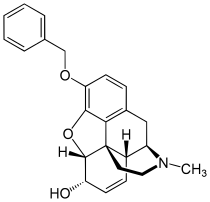

Codeine-dionine family

- 6-Monoacetylcodeine

- Benzylmorphine

- Codeine methylbromide

- Desocodeine

- Dimethylmorphine (6-O-Methylcodeine)

- Ethyldihydromorphine

- Methyldihydromorphine (dihydroheterocodeine)

- Ethylmorphine (dionine)

- Heterocodeine

- Isocodeine

- Pholcodine (morpholinylethylmorphine)

- Myrophine

- Thebacon

- Transisocodeine

Structures

| Codeine-dionine family | ||||

|---|---|---|---|---|

6-Monoacetylcodeine 6-Monoacetylcodeine |

Benzylmorphine Benzylmorphine |

Codeine methylbromide Codeine methylbromide |

Desocodeine Desocodeine |

Dimethylmorphine Dimethylmorphine(6-O-Methylcodeine) |

Ethyldihydromorphine Ethyldihydromorphine |

Methyldihydromorphine Methyldihydromorphine(dihydroheterocodeine) |

Ethylmorphine Ethylmorphine |

Heterocodeine Heterocodeine |

Isocodeine Isocodeine |

Pholcodine Pholcodine |

Myrophine Myrophine |

Transisocodeine Transisocodeine | ||